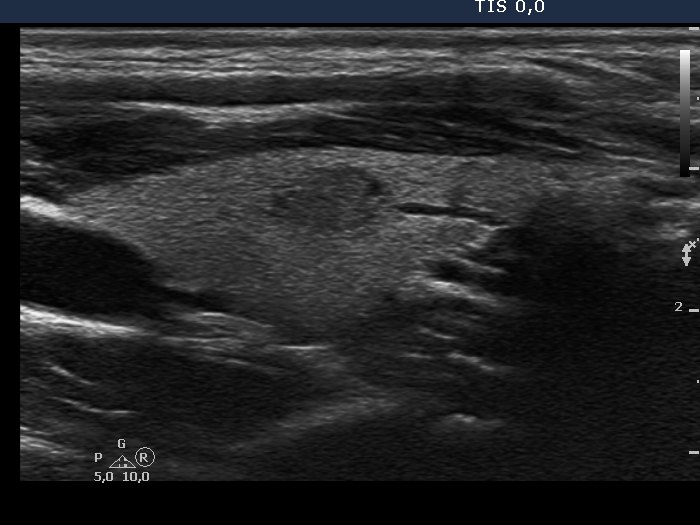

100 consecutive patients with papillary carcinoma - Case 2. (ultrasonographic picture 9)

Left lobe, longitudinal scan, enlargement.